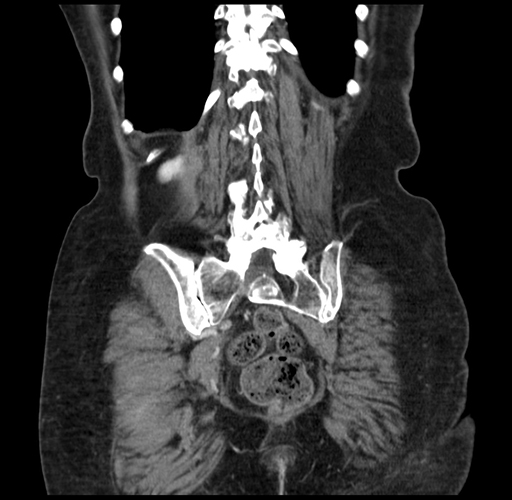

Pre-Chemo: Coronal Venous